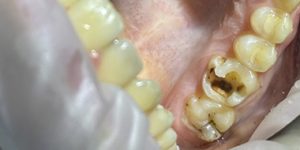

«Такое возможно?» — спросите вы. К сожалению, да. Потому что не всегда возможно убрать инфекцию полностью. Иногда доктор пытается сохранить наибольшее количество своих тканей зуба, и тогда возможен кариес на пломбированном зубе после лечения. Часто кариес после пломбирования зуба может появиться, если использовались не очень качественные пломбировочные материалы, например, те, что выделяются нашей системой ОМС. Как определить, что у вас кариес под пломбой на рентгене? Если вы проведете рентгенодиагностику, то под яркой рентгеноконтрастной пломбой можно увидеть темную полосу или поднутрение с неровными контурами различной глубины поражения.

Работы наших специалистов по лечению кариеса под пломбой